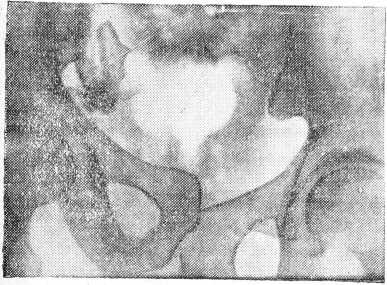

На рентгеновском снимке (рис.) нарушение целости левого края крестцовой кости, диастаз лобкового соединения. Вся лев я половина таза смещена кверху. Верхне-передне-подвздошная кость левой стороны выше на 3 см; линия Розер Нелатона проходит выше пупка.

Рис.

Один из наших случаев представляет редко встречающийся вывихо-перелом таза, где имеется отрыв хряща лобкового сочленения. Перелом левого края крестцовой кости с разрывом сумки передних и задних связок в крестцово-подвздошном сочленении. Напалков объясняет подобное смещение передачей действующей силы на концы костей по продолжению (рессорность), а так как концы укреплены подвижно, то получается разрыв связок. Следовательно, разъединение лобковых костей, разрыв сумки, передних и задних связок крестцово - подвздошного сочленения, а так же прочего связочного аппарата костей таза ведет к смещению разъединенной половины действием комплексных сил (мышц живота и спинных мышц) в краниальном направлении. Перелом крестцовой кости надо объяснить непосредственным воздействием насилий на ее край. Расхождение костей симфиза, по всей вероятности, произошло вследствие сильного сокращения приводящих мышц бедра в момент падения. У больного наблюдался перелом левого края крестцовой кости с повреждением нервных корешков и травмой мочевого пузыря (разрыва не было), результатом чего была временная задержка мочи и сильные продолжительные боли в крестце. Большая гематома, перешедшая в нагноение, затрудняла применение реальных методов лечения (наложение повязки, вытяжение и др. мероприятия в первое время).